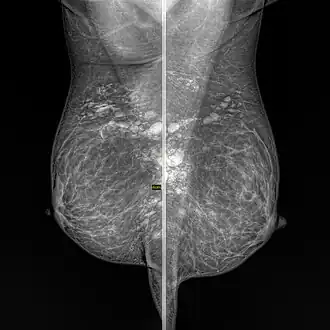

Silicone granuloma

Silicone granulomas are a skin condition that occur as a reaction to liquid silicones, and are characterized by the formation of nodules.[1]: 46

Formation of a granuloma is a common tissue response to a range of foreign bodies. Silicone can be directly injected into tissue as part of a cosmetic procedure or it can leak from silicone implants. The formation and consequences of silicon-induced granulomas is not well described or understood. The extent of damage that they cause is controversial.[2]

- Breast: Granulomatous mastitis[9][10]